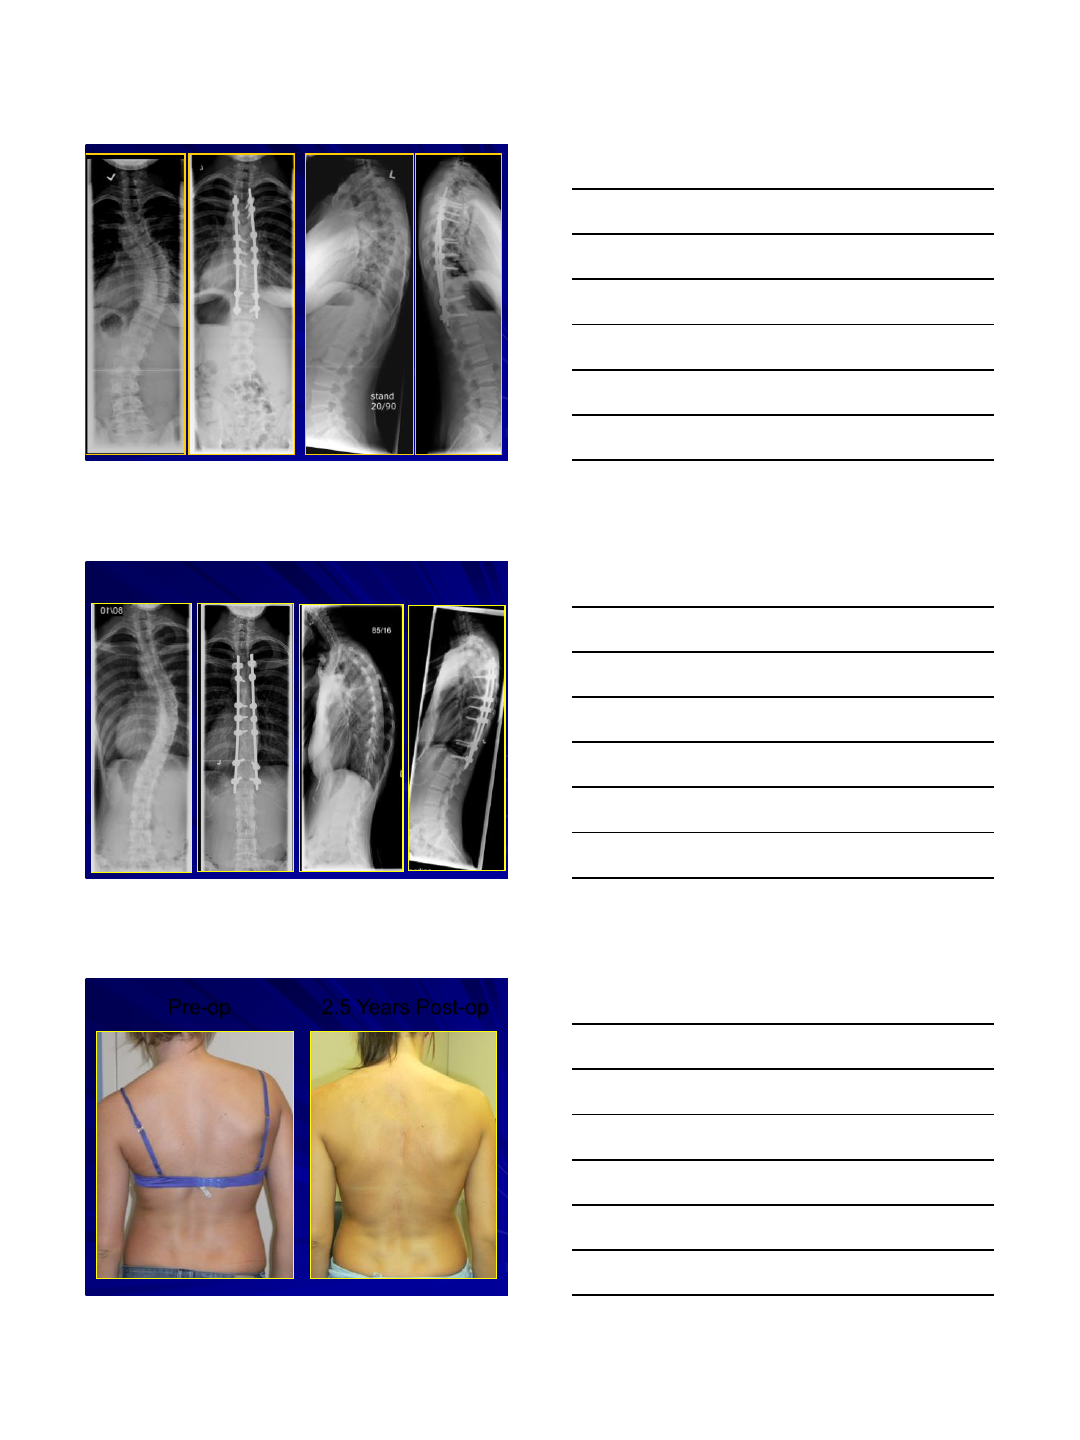

Pre-op 2.5 Years Post-op

2.5 Years Post-op

Pre-op